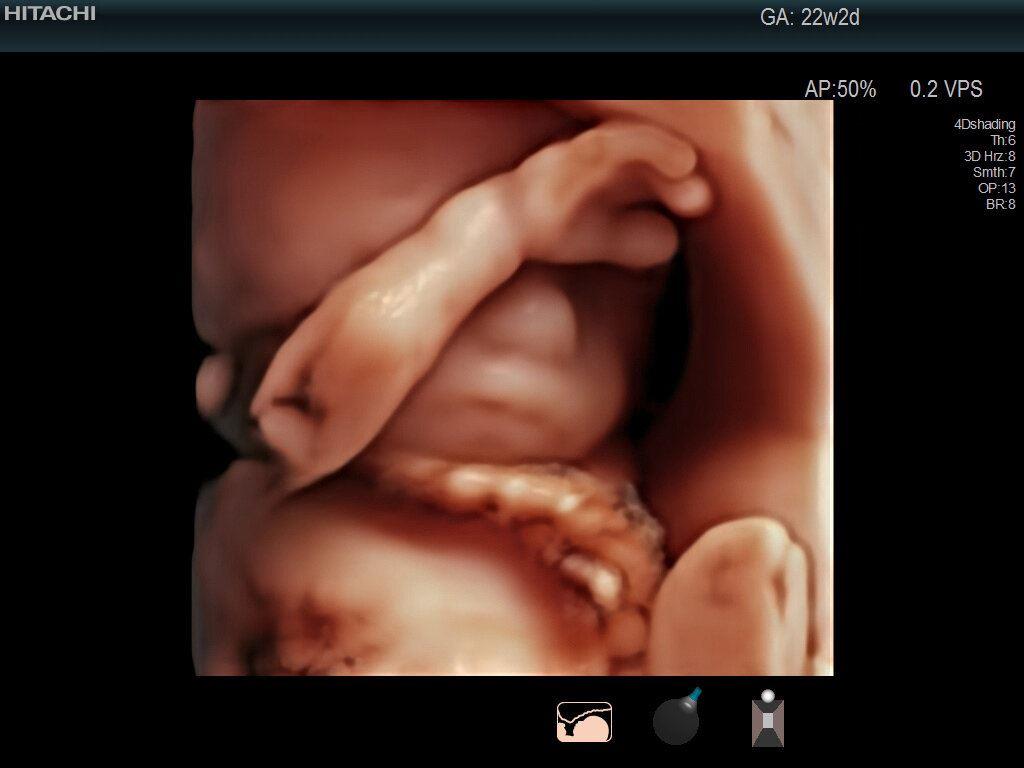

- 高層次超音波胎兒異常篩檢(檢查週數為懷孕20~22週,在產前診斷子宮內的胎兒是否有先天結構性異常)

- 胎兒4D影像